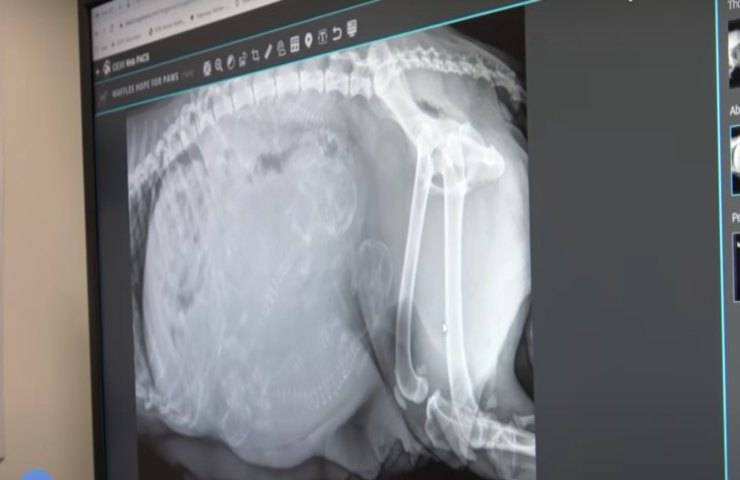

La prima tappa è stata quella del veterinario che ha deciso di fare chiarezza sulla situazione con un’ecografia nella quale è sembrato subito evidente che al parto non sarebbe mancato molto. L’animale era infatti al suo 57esimo giorno di gestazione a fronte dei 60-63 previsti per il parto, motivo per cui non vi era tempo da perdere e bisognava trovare per lei una casa.